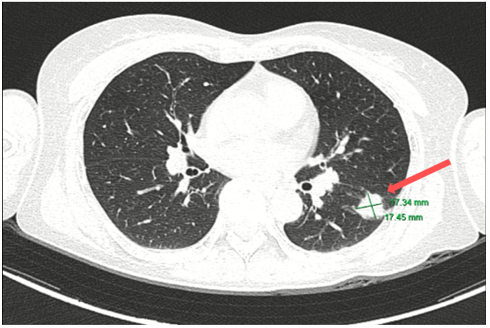

CT ngực (05/2024):

Hình 2: Hình ảnh tốt đặc ở phân thùy S6 phổi trái, đường kính 17 mm, bờ tua gai. Không thấy hạch trung thất to.